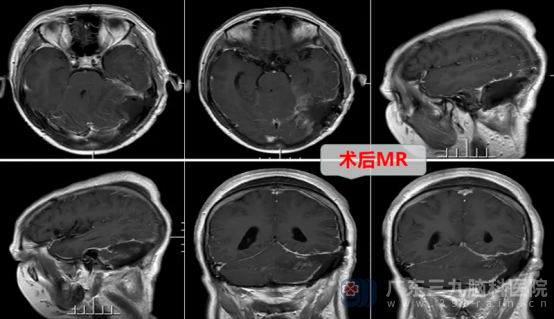

术后头颅MR显示,后颅窝左侧枕部-左侧小脑幕下病变已全切除。术后病理结果为形态学符合纤维型脑膜瘤,CNS WHO 1级。经过一段时间住院治疗后,王女士恢复良好,能够平稳走路,已经顺利出院。